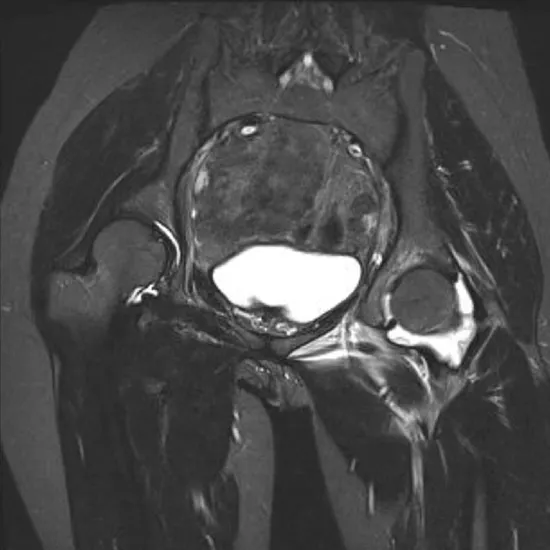

Right hip joint contrast-enhanced MRI images the bones of the hip joint as well as the surrounding muscles, tendons, ligaments, and blood vessels. Therefore, by making the interior organs more visible, the contrast improves the sensitivity and diagnostic accuracy of the MRI scan.

This test is utilized to identify hip joint arthritis, hip dislocations, and any fractures in the bones that make up the hip joint.